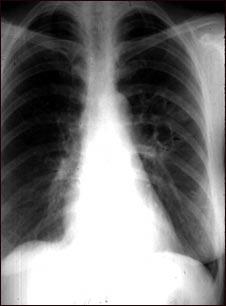

Coccidioidomicosis - radiografía de tórax

Esta radiografía de tórax muestra los efectos de una infección micótica, la coccidioidomicosis. En el centro del pulmón izquierdo (visto en el lado derecho de la figura) hay múltiples cavidades de pared delgada (vistas como áreas claras de la imagen) con un diámetro de 2 a 4 centímetros. Al lado de estas áreas claras, se encuentran áreas de parches claros con bordes irregulares y poco definidos.

Otras enfermedades que pueden explicar estos hallazgos en una radiografía son, entre otras: abscesos pulmonares, tuberculosis pulmonar crónica, histoplasmosis pulmonar crónica y otras.